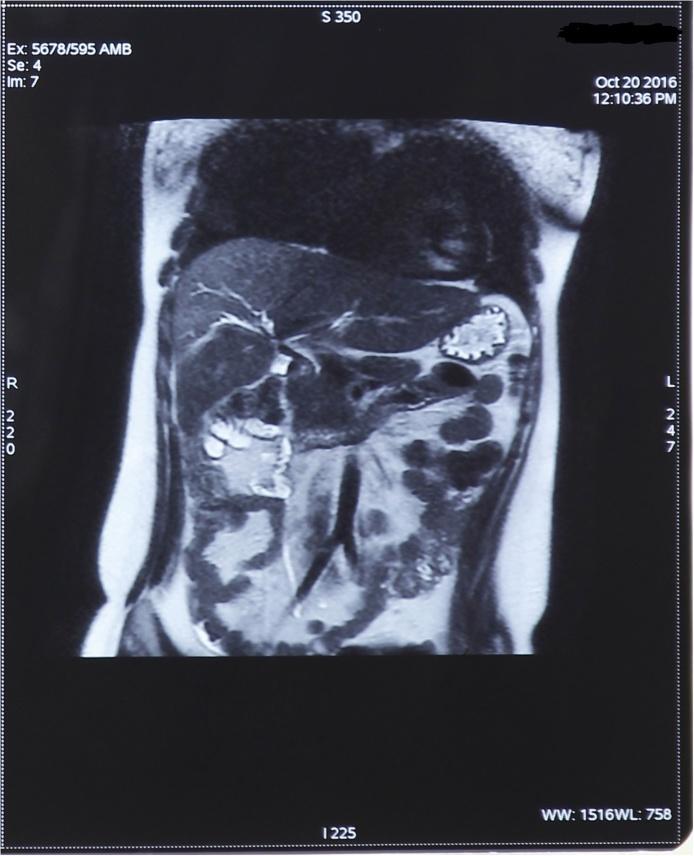

A 21-year-old woman suffered from iatrogenic high transectional lesion of both hepatic ducts during laparoscopic cholecystectomy in a local hospital. Iatrogenic injury was not immediately recognized. Ten days later due to patient complaints and large amount of bile in abdominal drain sac, second surgery was performed to evacuate biloma. Symptoms reappeared again, together with bile in abdominal sac, and then patient was sent to our Clinical Center. After performing additional diagnostics, high type (Class E) of iatrogenic hepatic duct injury was diagnosed. A revision surgical procedure was performed. During the exploration we found high transection lesion of right and left hepatic duct, and we decided to do Roux-en-Y hepaticojejunostomy. We created a part of anastomosis between the jejunum and liver capsule with polydioxanone suture (PDS) 4-0 because of poor quality of the remaining parts of the hepatic ducts. We made two separate hepaticojejunal anastomoses (left and right) that we partly connected to the liver capsule, where we had a defect of hepatic ducts, without Witzel enterostomy and transhepatic biliary stent. There were no significant postoperative complications. Magnetic resonance cholangiopancreatography (MRCP) was made one year after the surgical procedure, which showed the proper width of the intrahepatic bile ducts, with no signs of stenosis of anastomoses.

一名21岁女性在当地医院行腹腔镜胆囊切除术时发生医源性高位肝管横断损伤。医源性损伤当时未被立即识别。十天后,由于患者主诉及腹腔引流袋内有大量胆汁,遂行二次手术以引流胆汁瘤。症状再次出现,腹腔引流袋内又有胆汁,随后患者被转至我院临床中心。在进行进一步检查后,诊断为高位(E级)医源性肝管损伤。遂行修复性手术。术中探查发现左右肝管高位横断损伤,决定行Roux-en-Y肝空肠吻合术。由于肝管剩余部分质量较差,我们用4-0聚二氧六环酮缝线(PDS)在空肠与肝包膜之间创建了部分吻合。我们进行了两个独立的肝空肠吻合(左右侧),部分连接至肝包膜上肝管有缺损的部位,未行Witzel造口术及经肝胆汁支架置入。术后无明显并发症。术后一年行磁共振胰胆管造影(MRCP)检查,结果显示肝内胆管宽度正常,吻合口无狭窄迹象。